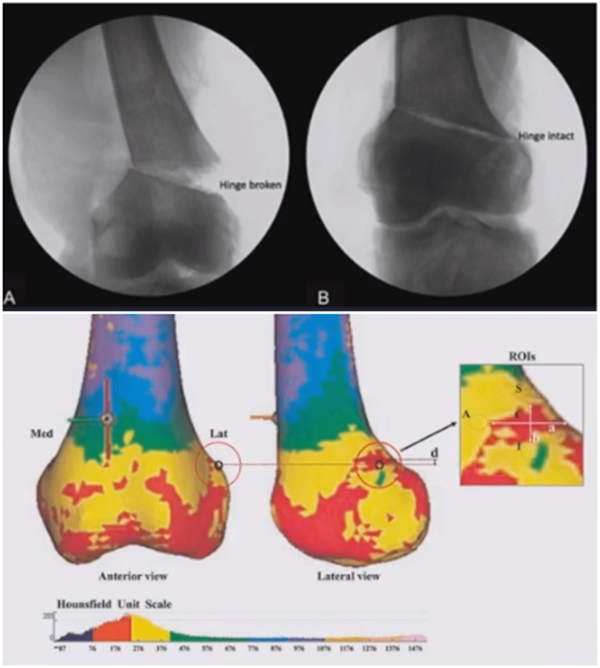

(1)合页骨折

对于术中出现的合页骨折,此时还有一定的稳定性,可以调整力线固定以后,由前外向后内打一根防旋螺钉,这样仍然是比较稳定,术后康复计划与正常一样。

对于术中合页骨折,但非常不稳定、无法控制力线的情况,可以由外侧向股骨外髁打入一枚2.0的克氏针,因为克氏针具有一定弹性,相当于重建合页临时稳定性,在此基础上再去调整力线,做固定。

术后做植骨,早活动、晚负重,避免做扭转活动。

晚期出现的合页骨折,此时力线已经改变,只能进行翻修。

影像学检查显示左侧出现合页断裂。